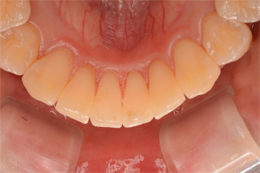

マウスピース矯正装置にて上下顎の矯正を行いました。

足りないスペースは側方への歯列拡大とIPR(歯の間の削り込み)を行い矯正しました。